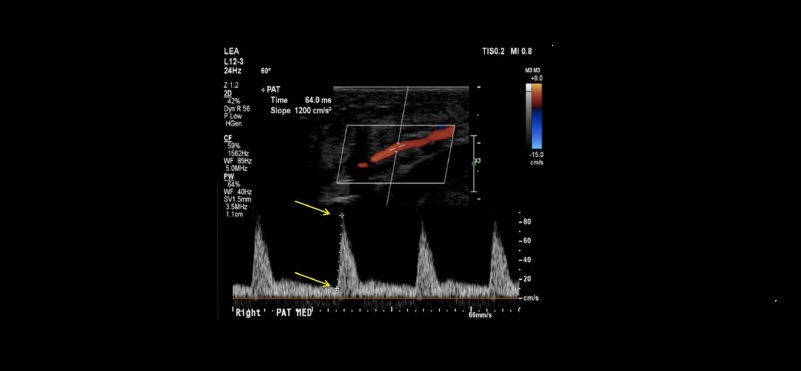

Pedal Acceleration Time (PAT)

Duplex Ultrasound Defined Angiosome With the Use of Pedal Acceleration Time as a Predictor to Wound Healing